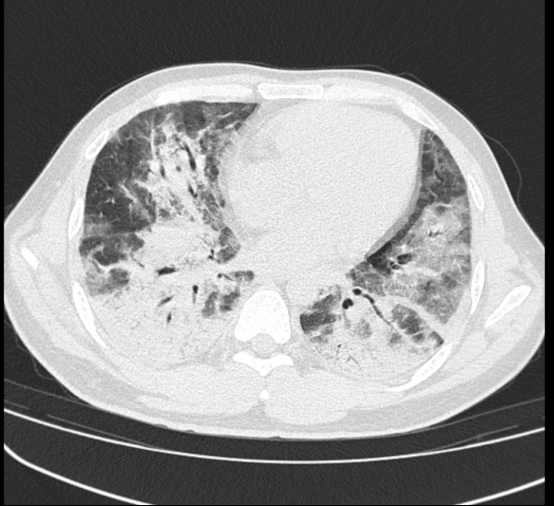

近期,东莞38岁的袁先生因“发热、咳嗽、喘息”,来到东莞市石碣医院治疗。刚开始他以为只是普通的感冒,“熬”一下就过去了,但胸部CT检查结果却让大家吃惊:已经“大白肺”。

健康的肺是由通气功能正常的肺泡组成,这样的肺泡充满了空气,在X光和CT上都是透光的,并且显示为黑色。

但如果肺部有严重的疾病,比如重症肺炎、肺部肿瘤或者有大量的积液,这时在X光和CT上就表现为一种烟雾笼罩的白色,即我们俗称的“白肺”。